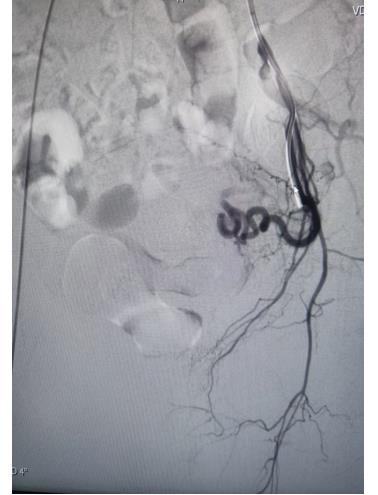

左側(cè)子宮動(dòng)脈栓塞前后對(duì)照

子宮動(dòng)脈栓塞術(shù)屬于血管介入性治療,方法是于股動(dòng)脈穿刺進(jìn)針插入導(dǎo)管,在X射線造影下定位進(jìn)入兩側(cè)子宮動(dòng)脈,注入栓塞劑完全栓塞子宮動(dòng)脈,從而達(dá)到止血或讓子宮肌瘤和病灶缺血壞死的目的;2022年12月6日,在崔旭輝主任、孟慶槐副主任醫(yī)師、馬力主治醫(yī)師等我院介入團(tuán)隊(duì)協(xié)作下,成功為患者進(jìn)行了雙側(cè)子宮動(dòng)脈栓塞術(shù),術(shù)后患者子宮異常出血停止,效果立竿見影,患者病情恢復(fù)良好。